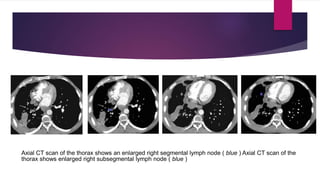

Axial CT scan of the thorax shows an enlarged right segmental lymph node ( blue ) Axial CT scan of the

thorax shows enlarged right subsegmental lymph node ( blue )

Axial CT scanof the thorax shows an enlarged right segmental lymph node ( blue ) Axial CT scan of the thorax shows enlarged right subsegmental lymph node ( blue )